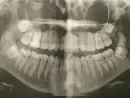

Растет зуб мудрости. Боли беспокоят от 3 до 5 дней в году. Пользуюсь мазью "Холисал", чтобы как-то снять боль. Сделала рентген челюстей, сказали, что зубы мудрости еще не сформировались, и удалять пока, что не будут. Меня волнует, что зуб может сейчас давить на здоровые зубы, и что может произойти скученность зубов.

Прикрепленые фото